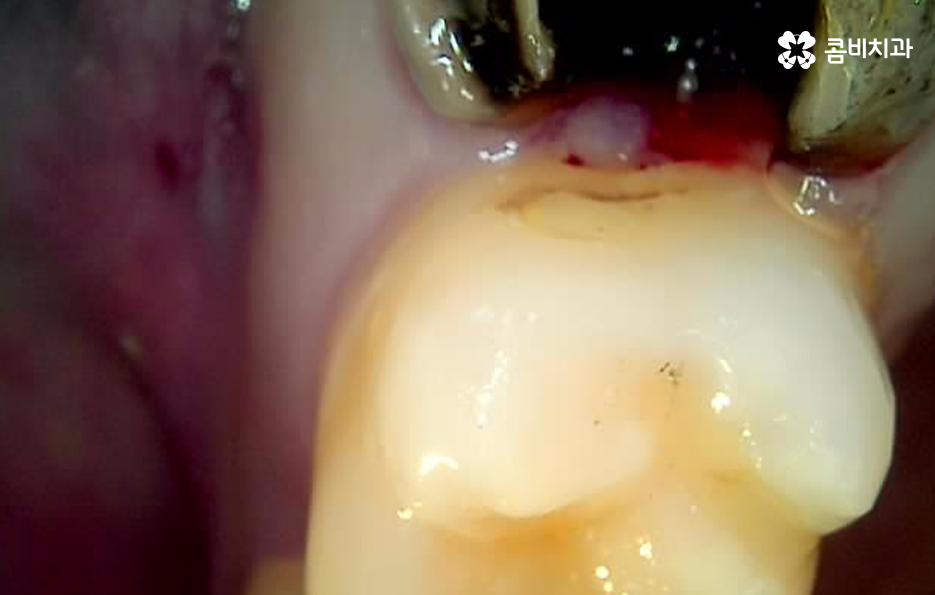

하지만 위 사진에서 보시는 것처럼 치아에서 통증은 못느끼더라도 2차 충치가 발생되어 뒤늦게 치아 내부의 충치에 대해 알게 되면 이미 치아 뿌리까지 충치가 심각하게 진행되어 크라운 재치료가 어려울 정도로 손상이 진행된 경우도 많으며 결국 어금니 발치후 임플란트 치료로 이어질 수 있어요

신경치료 후 크라운을 씌우게 되었더라도 치아의 뿌리 손상 정도와 치아의 잔존량에 따라서 크라운의 재치료, 즉 재신경치료와 같은 방법으로 자연치아를 보존하는 방법도 있지만 치료 시기를 놓치게 된다면 어금니 발치후 임플란트 시술을 받아야 하기 때문에 오래된 보철물은 주기적으로 검진을 통해 필요하다면 재치료 시기를 놓치지 마시길 바라고 있어요

위 치료 사례의 경우 크라운 내부의 2차 충치로 인해 치아 발치를 진행한 사례이기 때문에 치아 상실의 원인이 충치인 경우에는 잇몸 뼈의 상태 자체는 양호한 경우가 많이 있는데요